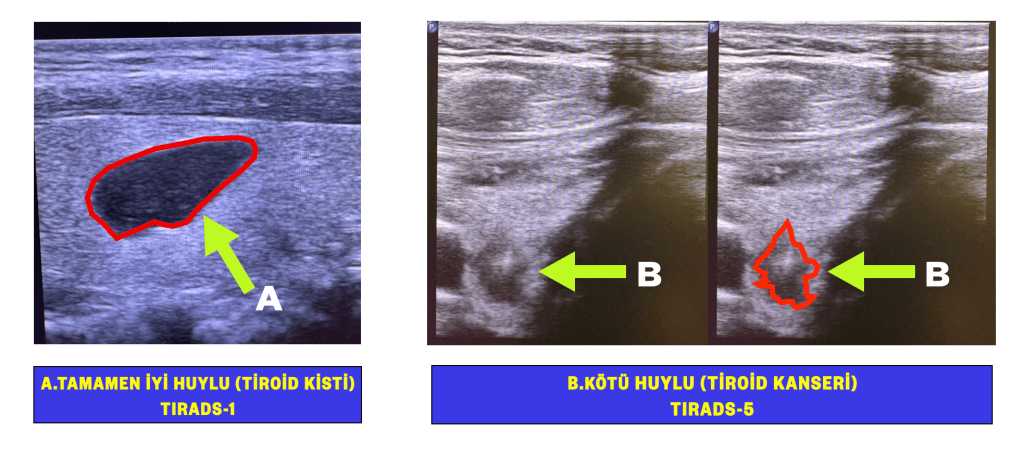

Tiroid nodülü bulunan hastalarda hangi tip nodüllerden parça alınacağı, deneyimli radyologlar tarafından yapılan ultrasonografiler ile belirlenmektedir. Bu nedenle biyopsi kararını vermede, iyi bir tiroid ultrasonografisi muayenesi şarttır.

Maalesef klinik pratikte, riskli nodüllerden biyopsi yapılmadığını veya riski son derece düşük nodüllerden ise parça alındığını görebiliyoruz. Bunun önüne geçilmesi ve tiroid biyopsi işleminin standardize edilmesi amacıyla, Amerikan Radyoloji Cemiyeti (ACR-TIRADS), Avrupa Tiroid Cemiyetinin (EU-TIRADS) veya Kore Tiroid Radyolojisi Cemiyetinin (K-TIRADS) gibi cemiyetlerin yayınlanan kılavuzları takip edilerek biyopsi işlemine karar verilmelidir.

Biyopsi kararı verilebilmesi için, bu kılavuzların belirttiği noktaların ultrasonografi raporunda detaylandırılması şarttır. Ayrıca rapor sonucunda, biyopsi gerekip gerekmediğini gösteren özel bir skorlama sistemi eklenmelidir.